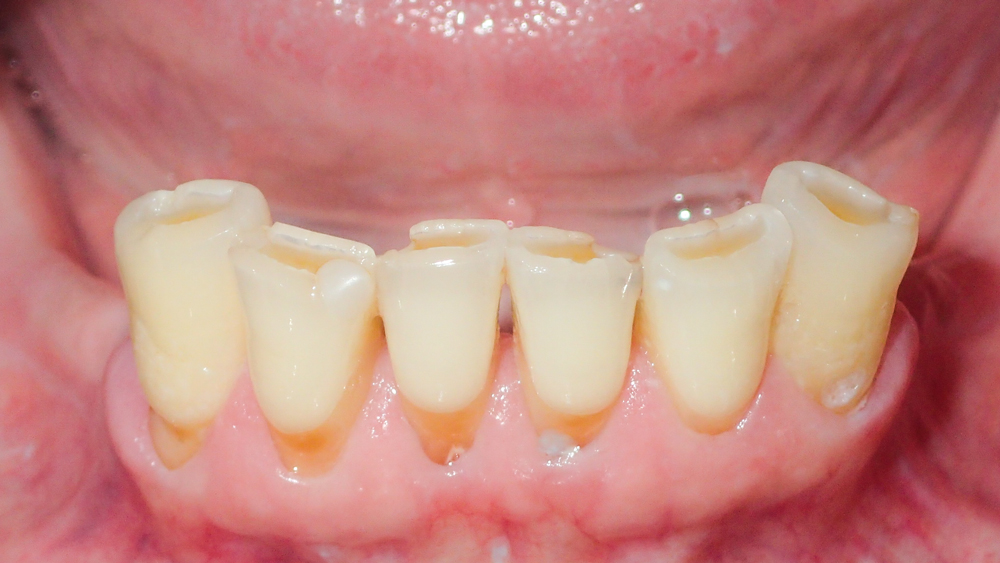

This patient was unhappy with the esthetics of her existing upper denture as well as the discomfort and instability caused by her loose-fitting mandibular partial denture. Although her concerns with the maxillary denture could be addressed with a new, more esthetic appliance, she preferred implant treatment for her mandible, where a fixed solution was needed to adequately restore function, stability and comfort.

The patient’s remaining mandibular teeth were extracted followed by immediate implant placement and delivery of a fixed provisional appliance. After integration of the implants, the prosthetic designs for the new upper denture and lower implant restoration were determined in tandem. Ultimately, the dual-arch restorations addressed the functional and esthetic challenges of the case while staying within the financial means of the patient, demonstrating the benefits of a flexible, multifaceted approach to restorative dentistry.